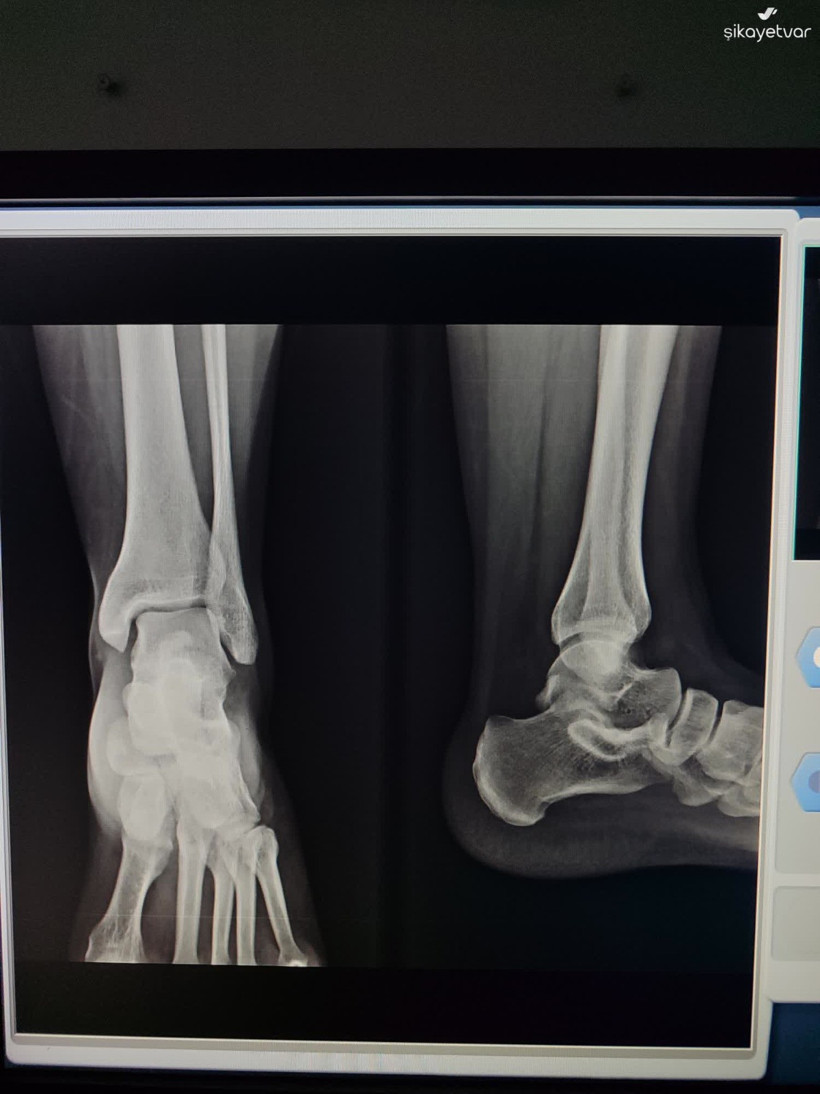

Kocaeli’de bir vatandaşın Şikayet Var adlı internet sitesinde yaptığı paylaşım, “Acil serviste kim acil?” sorusunu yeniden gündeme taşıdı. Körfez Devlet Hastanesi Acil Servisi’nde yaşandığı iddia edilen olay, sosyal medyada ve kamuoyunda tartışma yarattı. Şikayet Var platformunda yer alan paylaşıma göre olay, 13 Aralık 2025 Cumartesi gecesi saat 22.30 sıralarında Kocaeli Körfez Devlet Hastanesi Acil Servisi Triaj bölümünde yaşandı. Vatandaş, eşinin ayağında ya da ayak bileğinde çatlak olabileceği şüphesiyle hastaneye başvurduklarını ve acil olarak röntgen çekilmesi gerektiğini belirttiğini ifade etti.

13.12.2025 tarihinde saat 22.30 sularında, eşimde kırık ya da çatlak olabileceği şüphesiyle Kocaeli Körfez Devlet Hastanesi Acil Servis Triaj Bölümüne başvurdum. Acil olarak röntgen çekilmesi gerektiğini belirtmeme rağmen, triajda bulunan bir erkek ve bir kadın personelin ilgisiz ve laubali tavırlarıyla karşılaştım. Durumu defalarca anlatmama rağmen, yalnızca yeşil alana yönlendirilmekle yetindiler ve sürece dair hiçbir şekilde yardımcı olmadılar.